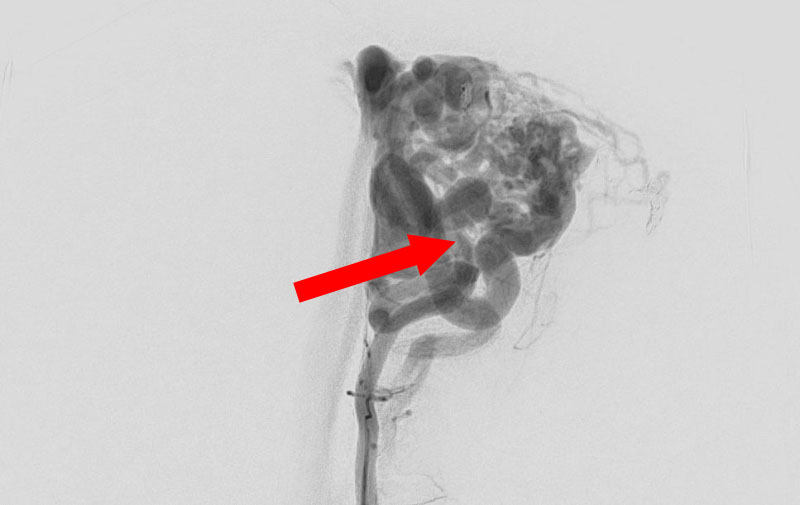

No.1594 手術前

No.1594 手術中

No.1594 手術後

'25年11月

くも膜下出血

破裂性内頚動脈解離

40代

救急外来